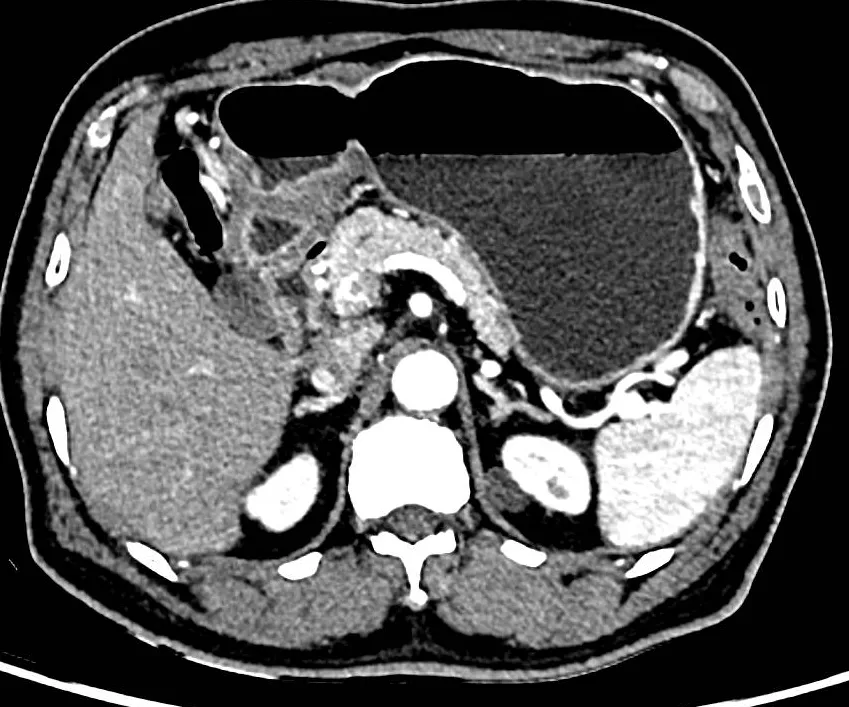

活检病理:(胃角)中-低分化腺癌,Lauren分型为肠型。HP(+)。病变外周1cm四象限活检均未见肿瘤。腹部增强CT:胃壁未见明显异常,壁外未见肿大淋巴结。